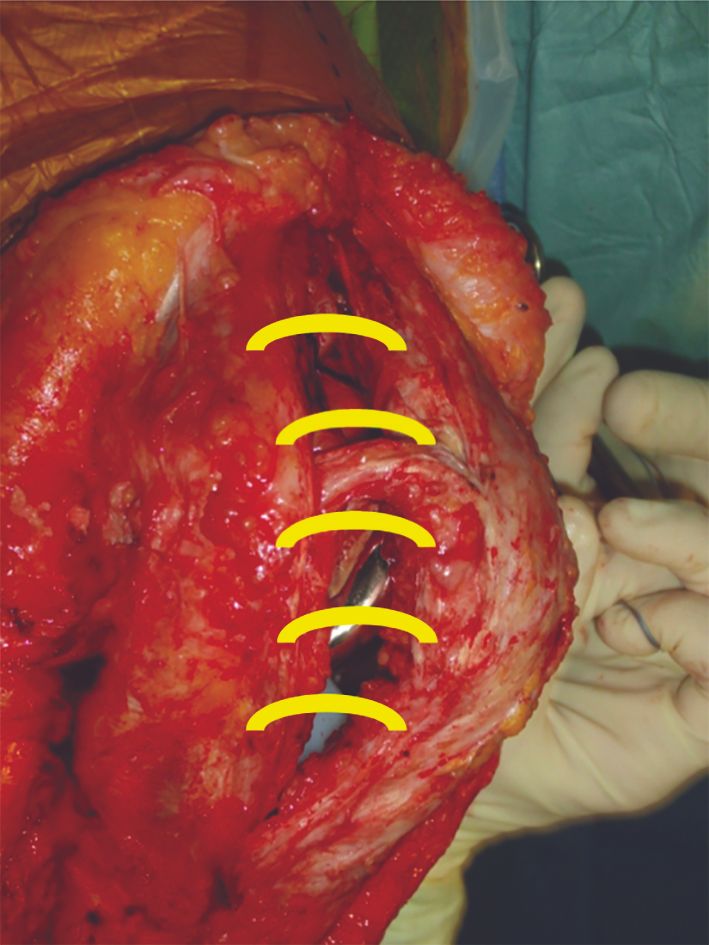

Patellar tilt is relatively common in descriptive studies.[17] It can cause painful impingement between the lateral patellar facet and femoral implant,[18] in turn due to improper patellar preparation (Figs. 3 & 4) or after medial approach with dehiscence of the capsular closure.[19]

In the specific case of painful patellofemoral impingement with a tilted or eccentric patella, solely reconstructing the MPFL can effectively recentre the patella. It may sometimes be combined with a lateral patella facetectomy to resolve the impingement and/or a lateral retinacular release to help recentre. Finally, patellofemoral instability after TKA with a native patella is a possible indication for secondary resurfacing. Persistent patellar instability during the procedure should prompt the surgeon to use one of the procedures described above.

The graft is passed outside the capsule. Finally, graft tension is adjusted at 30° of flexion. The patella must be centred and mobile, but not to the point of allowing dislocation. Make sure the patella is not too tight medially. Lateral movement of 7–9mm is recommended. The graft is then fixed with a resorbable interference screw.